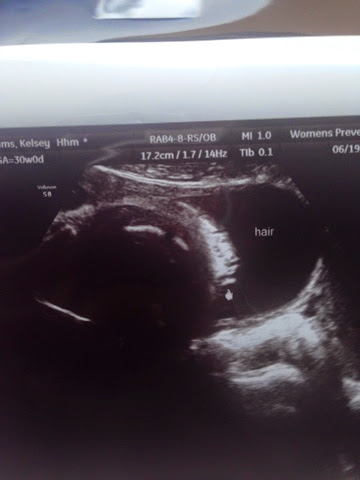

We had our fancy ultrasound this week and got to see a more realistic view of our little human hibernating in my belly. I can't wait to cuddle with her. She's already so big, measuring about 4 weeks ahead and in the 87th percentile... (This might hurt) I think she's starting to get cramped because she is twisting all of my insides around! I had my first round of Braxton Hicks contractions a few nights ago. If they don't come back, I won't be mad!

I have been experiencing a little Acid Reflux and my Dr. said it's not just an old wives tail. Acid Reflux is a sign of hair on baby. Sure enough there it was!